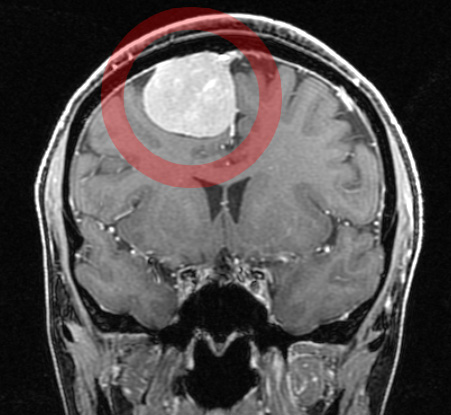

脳を包む膜から発生する腫瘍で、多くは良性ですが、悪性のものも存在します.

通常、硬膜を基盤として凸状に盛り上がりながら増大し、脳を圧迫することで様々な症状が出現します。

頭部CT検査、MRI検査、核医学検査、カテーテルを用いた脳血管撮影を行います。

それぞれの画像検査の結果を総合的に評価し、安全に治療を完遂するために必要な治療計画をお伝えいたします。